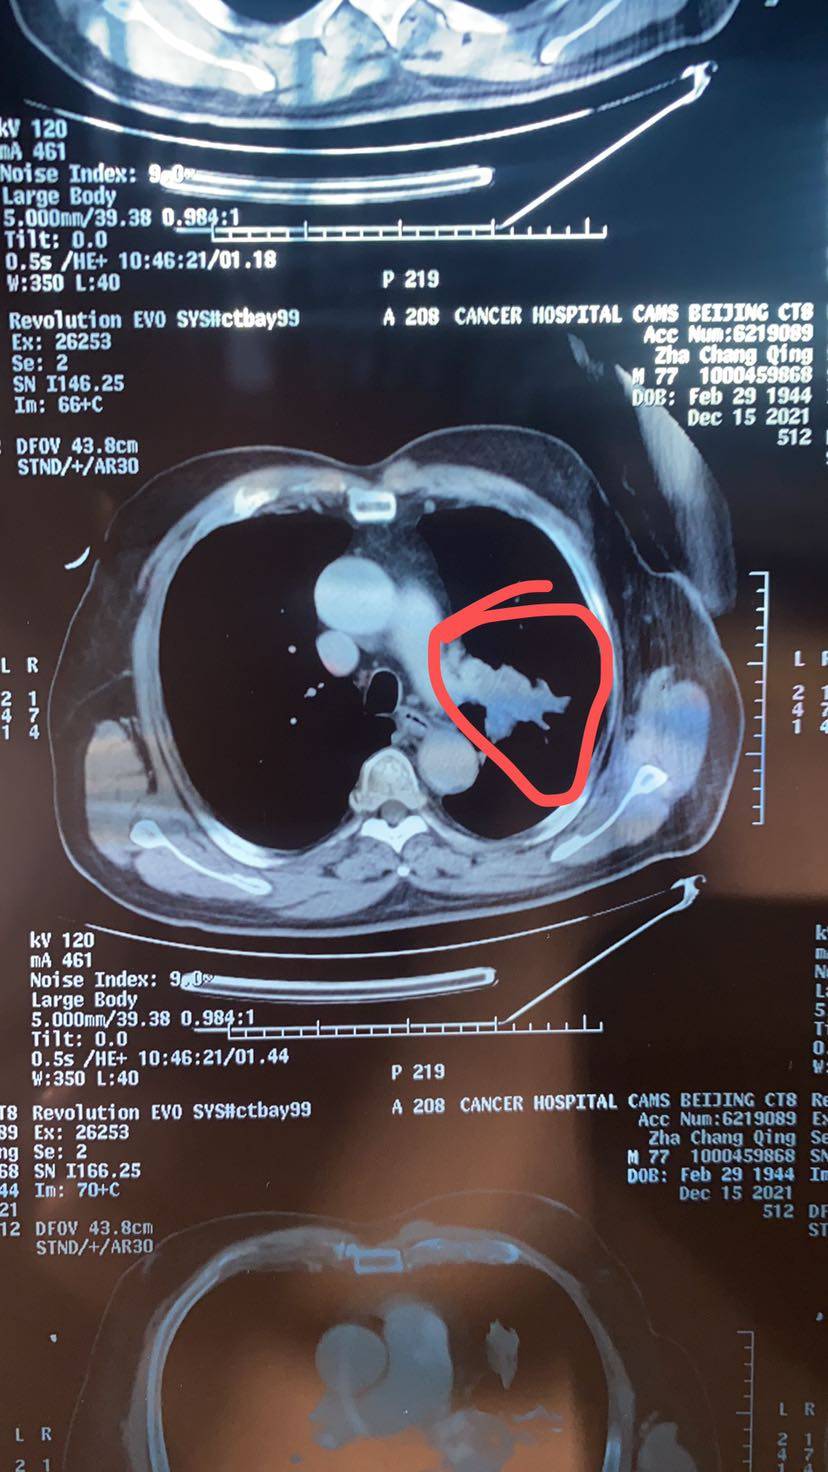

12月15日复查结果显示肿瘤缩小至5.8×3.3,淋巴结均有缩小,但是我看ct结果,自认为缩小挺多的,是我太乐观还是医生太保守了?

治疗后

看尺寸缩小不大,但是体积上就大了,一般医生都是量最大直径

打死癌细胞看片子还要看同一个层面的吧?你这不是同一层面怎么比较大小